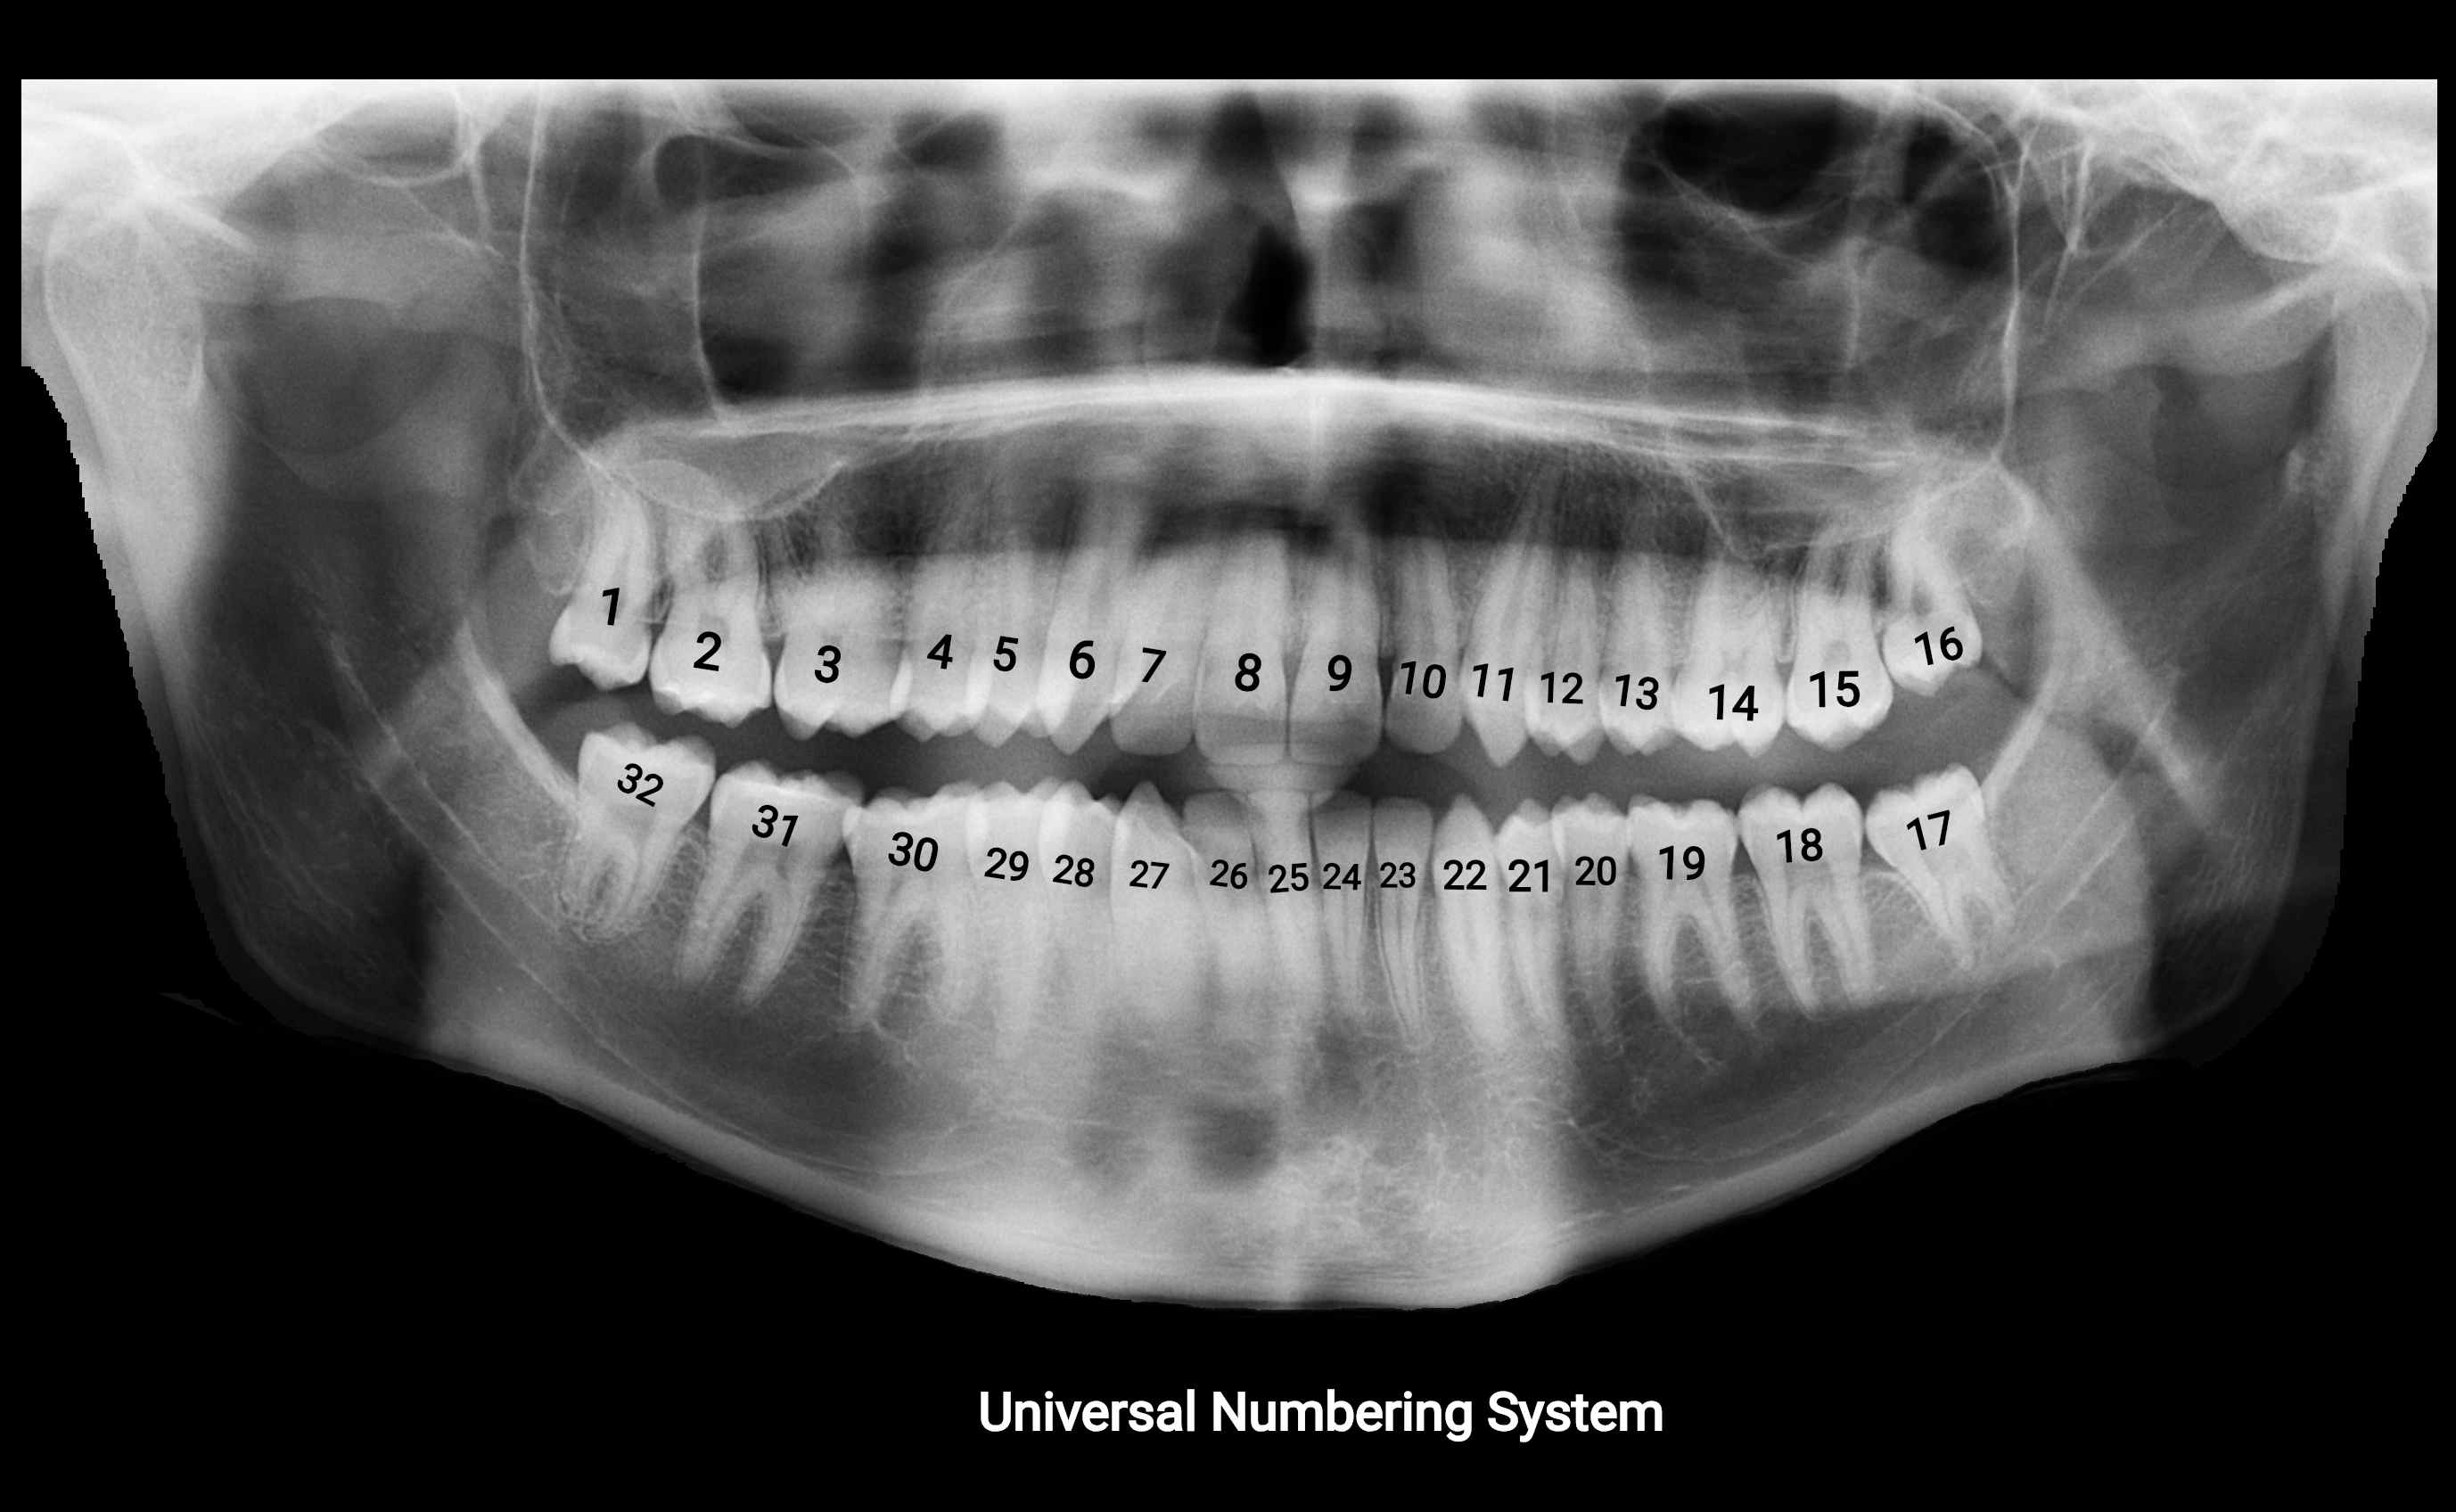

The alveolar process of the maxilla is the bony ridge of the maxilla that houses the upper teeth, extending from the anterior nasal spine to the maxillary tuberosity posteriorly. It consists of compact cortical bone on its outer surfaces and trabecular (cancellous) bone internally, with alveolar sockets (dental alveoli) forming individualized cavities for each tooth. The alveolar process develops in association with tooth eruption and resorption, adapting its shape and volume throughout life. It also forms part of the hard palate medially and contributes to the architecture of the midface, supporting the upper lip, cheeks, and nasal floor.